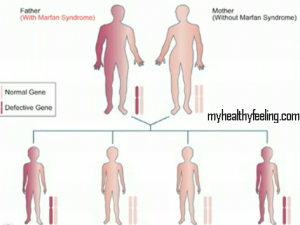

Marfan Syndrome is caused by a genetic defect. The gene that is impaired is FBN1 which has a connective protein called Fibrillin-1, it plays a crucial role in building the elastic tissue in the body. The genetic defect leads to overgrowth of bones, making them stretch long. This lead to tall height, limbs and arms. Also affected from Marfan Syndrome are the lung tissue, the eyes leading to cataract and other eye problems, the spinal cord tissue, the aorta, the main artery that circulates blood from the heart to various parts of the body. In fact, the syndrome can cause the aorta to stretch and weaken leading to aortic dilation or aortic aneurysm.

Though mainly Marfan syndrome is genetic disorder, in 30 percent of the cases, it has been seen that the person with the syndrome did not have a family history of the disease. Medically, these cases are termed ‘sporadic’ believed to have taken effect from an unstructured new gene defect.